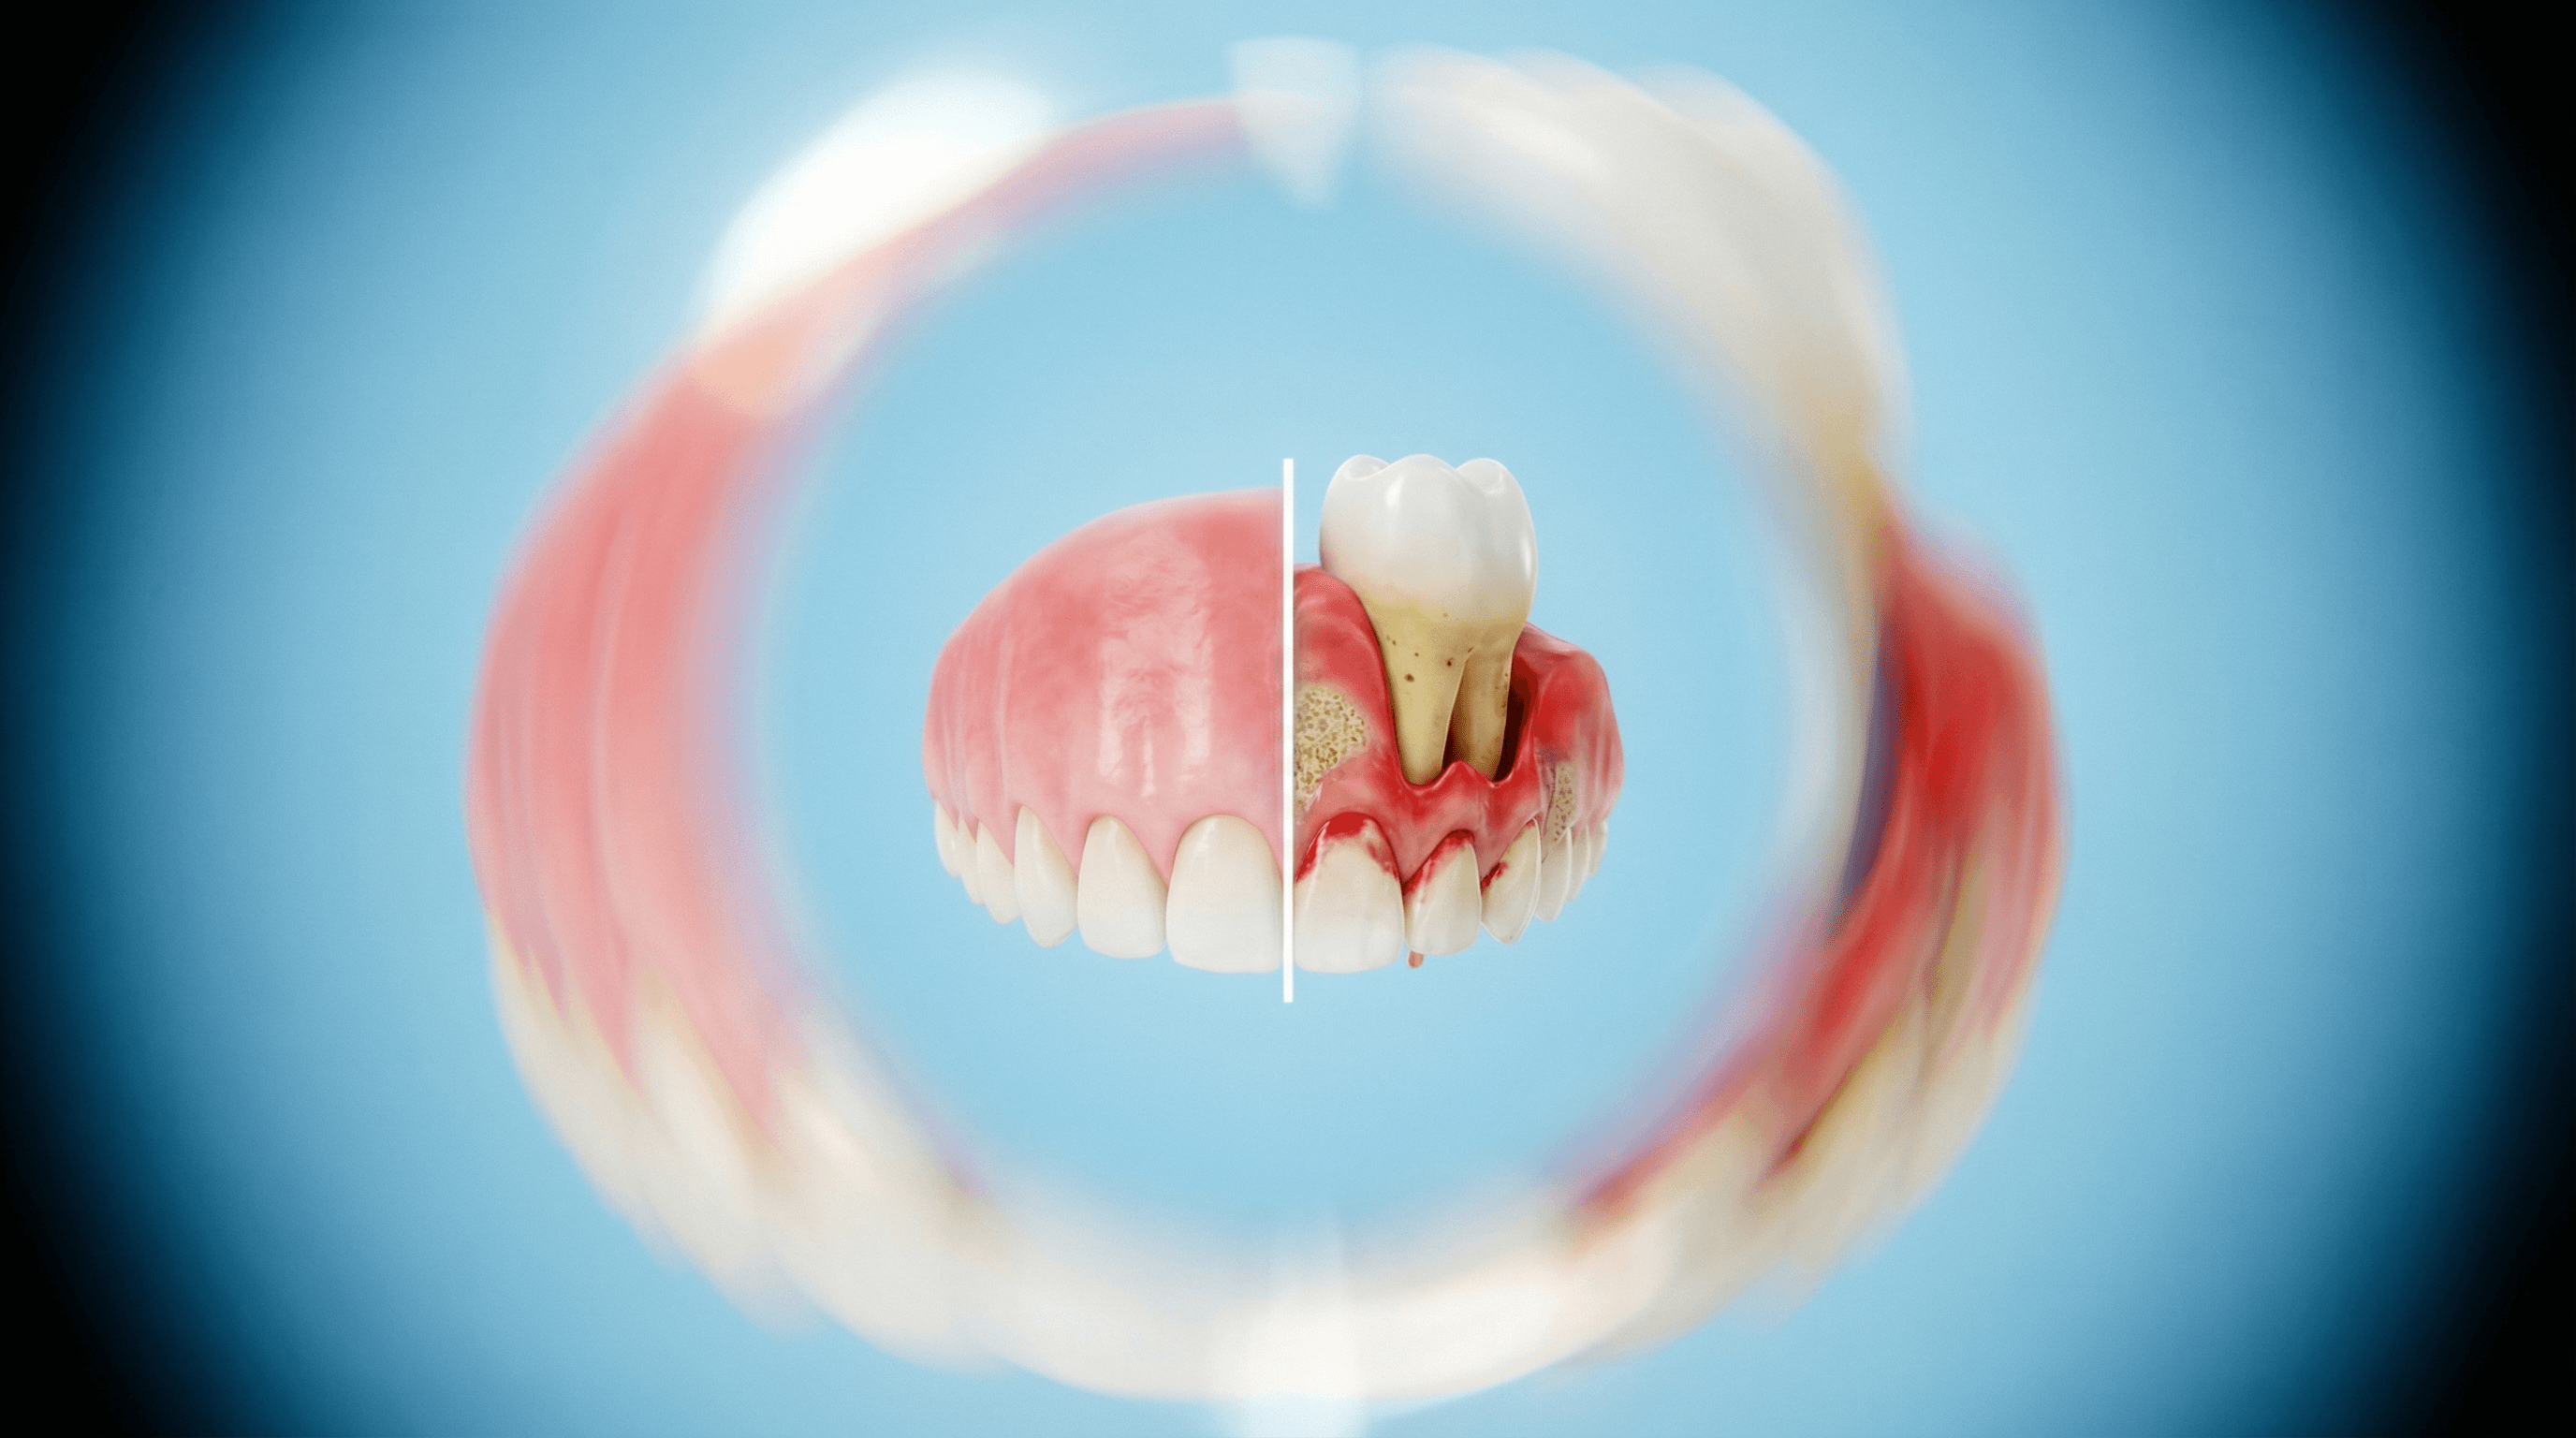

Parodontoza (boala parodontală) este o infecție bacteriană cronică care afectează gingiile și osul care susține dinții. Netratată, duce la retracție gingivală, pierdere osoasă și, în final, la căderea dinților.

- Sângerare gingivală - la periaj, la folosirea aței dentare sau spontan

- Gingii umflate și roșii - inflamație vizibilă și sensibilitate

- Retracție gingivală - dinții par mai lungi, rădăcinile devin vizibile

- Pungi parodontale - spații adânci între gingie și dinte